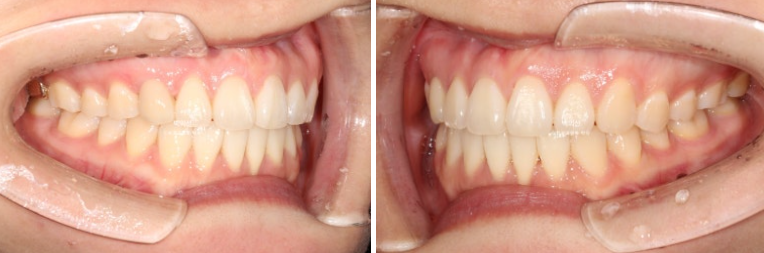

24.10~25.07

치료기간은 10개월 입니다.

주목할만한 점은 바로 치료 후 잇몸퇴축이 완화된 점입니다.

잇몸이 내려간 치아의 튀어나온 뿌리를 안으로 넣어줌으로써, 잇몸이 내려가 뿌리가 노출된 면적이 줄어들었습니다.

그외 소량의 치간삭제를 통한 틀랙트라이앵글의 개선도 눈에 띕니다.

개선된 미소와 스마일라인, 비스듬히 기울어진 앞니 각도의 개선

깔끔한 스마일라인이 돋보입니다.